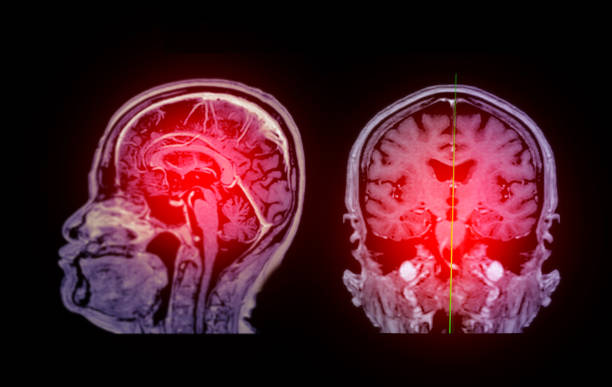

缺血性腦卒中,又稱(chēng)腦梗死,是一種因腦部血液循環(huán)障礙導致的腦組織壞死疾病。它給患者帶來(lái)的不僅是身體上的痛苦,更是心理上的巨大壓力。